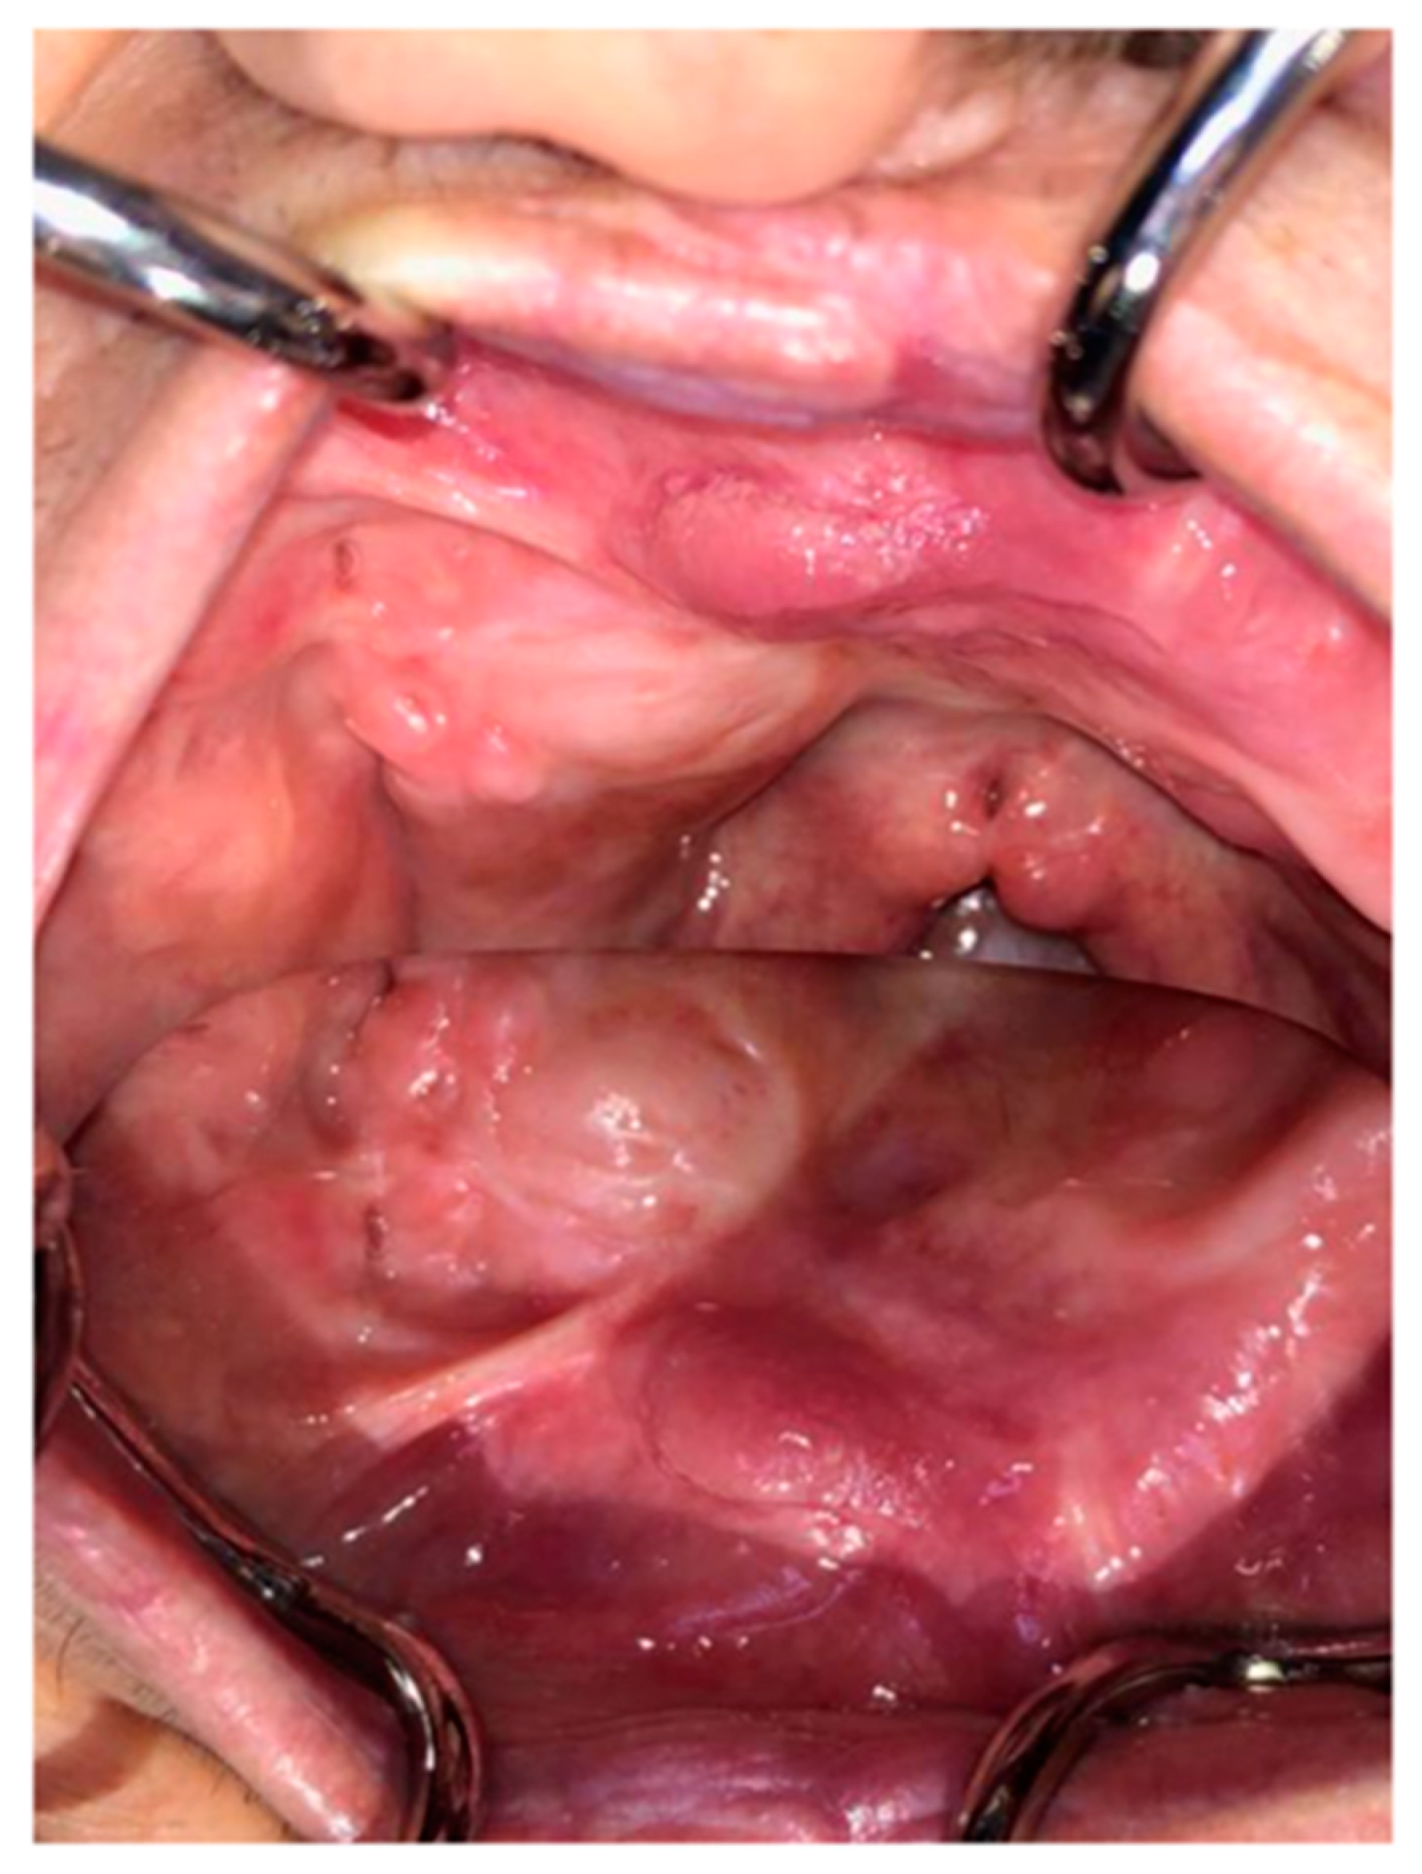

Once this initial phase is performed, the peduncle of the flap is dissected and the excess will be repositioned to partially reconstruct the area of the dorsum of tongue used. We prepared a case report and we have photographs of the clinical situation after 20 years the surgery was performed (Figure 2).

Figure 2.

We see the clinical situation after 20 years the surgery was performed.

With regards to the satisfactory results obtained, we can state that this method is predictable. It’s very important also the early diagnosis that allows the clinician to plan a therapeutic treatment that offers the best guarantees of success [2].